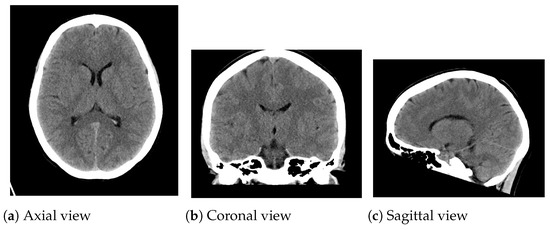

The introduced algorithm was analyzed on CT medical images from two clinical datasets. To this end, CT medical images (Figure 3) from the Radiopaedia dataset (Case Courtesy of A. Prof Frank Gaillard, Radiopaedia.org, rID 35508) were used in the experiments. These CT images appertain to a normal brain of a thirty-year-old woman. CT images were corrupted with various magnitudes of random impulsive noise (probability p [ 0.1 , 0.3 ] ) and Gaussian noise (standard deviation σ [ 10 , 30 ] ). For this purpose, the classical Gaussian-noise model and the random value impulsive noise [4] have been considered. The additive white Gaussian noise presents the following probability distribution:

Figure 3. CT medical images utilized in the experimentation. (a) Axial view: 1024 × 904 pixels; (b) Coronal view: 890 × 1024 pixels; (c) Sagittal view: 822 × 1024 pixels.